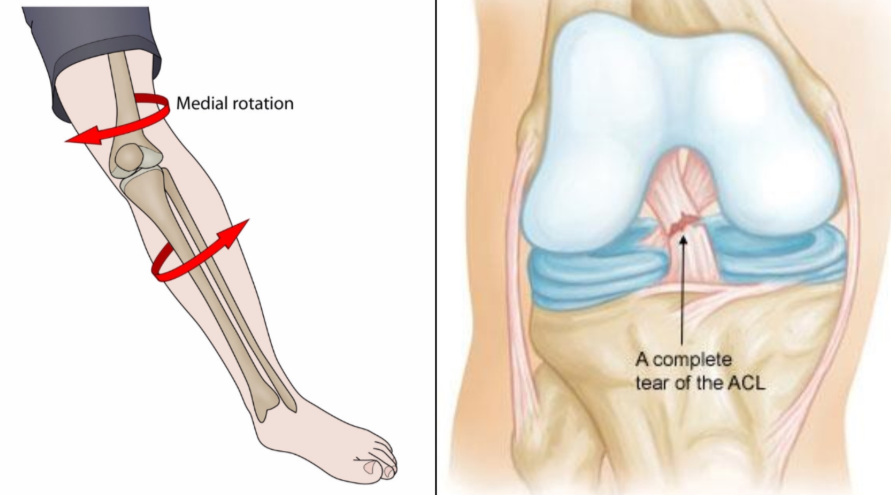

무릎이 갑자기 뒤틀리거나 급정지, 방향 전환하는 동작 중 발생.

점프 후 착지 시 무릎이 꺾이거나 충격 받을 때.

운동 중 비틀림, 충돌, 넘어짐 등 외상에 의한 직접적 손상.

무릎 과굴곡, 내반, 외반력이 가해질 때 손상 위험 상승.